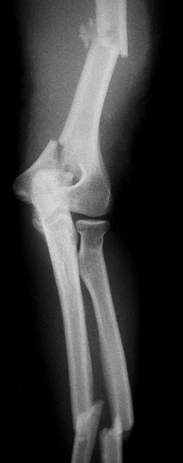

Grade II open, somewhat comminuted midshaft fracture of the left humerus (Fig. 14.2).![]() Figure 14.2. Figure 14.2.

Anteroposterior x-ray of the left arm, elbow, and forearm showing

fractures of the midshaft humerus, medial condyle of the humerus, and

midshaft radius and ulna.

Closed fracture of the medial condyle of the humerus (Fig. 14.2).

Grade II open transverse midshaft fractures of the left radius and ulna (Fig. 14.2).